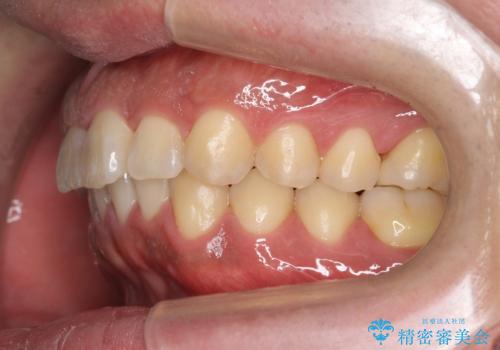

前歯のねじれを 1年かけずに矯正 インビザライン

- 前歯のねじれを主訴に来院。

インビザラインで治療しました。

前歯のねじれをセラミックで治そうとすると、抜髄といって、神経の治療が必要になる上、歯の幅も制限が出て理想的にはなりません。

保定の必要がありますが、天然歯を並べる矯正治療では、治療後の心配事が非常に少なく、保存的な処置となります。